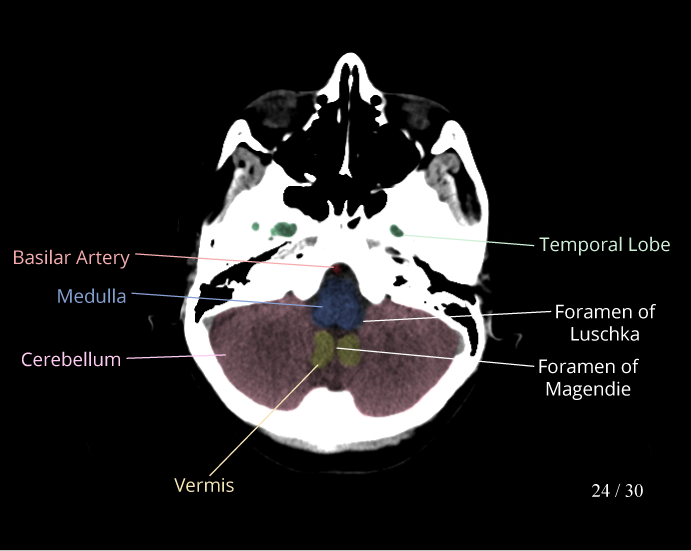

CT Brain Anatomy